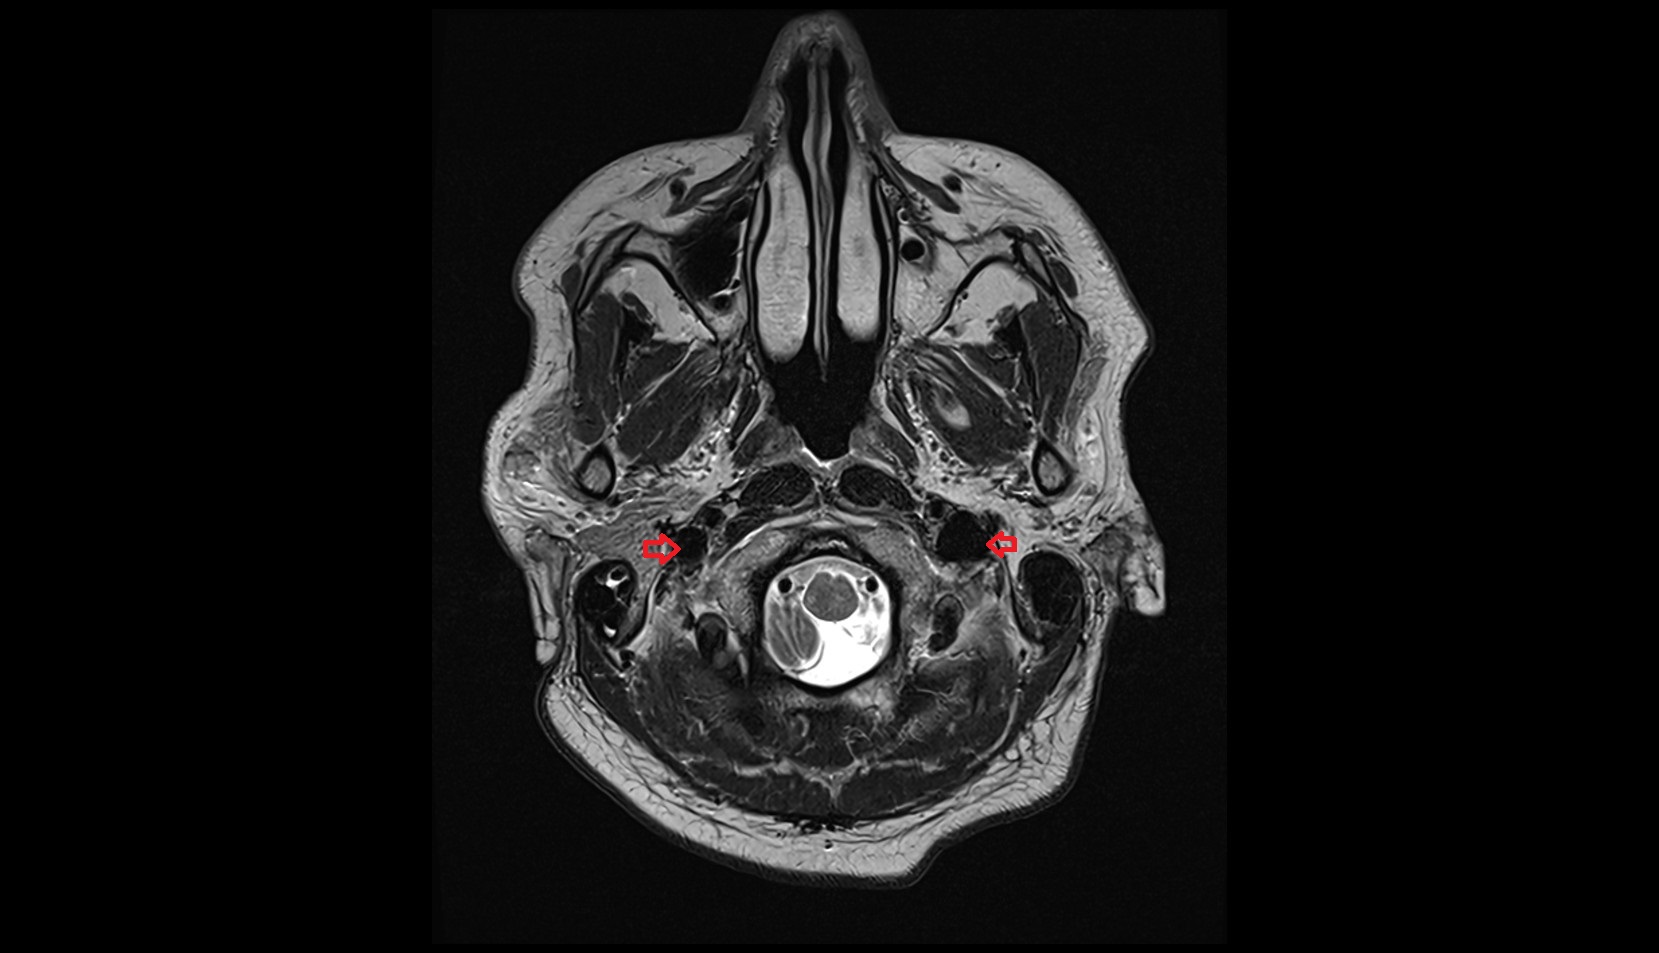

- Internal carotid artery (cervical part)

- Internal carotid artery (petrous part)

- Carotid canal